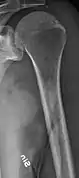

The diagnostic examination of a person with suspected multiple myeloma typically includes a skeletal survey. This is a series of X-rays of the skull, axial skeleton, and proximal long bones. Myeloma activity sometimes appears as "lytic lesions" (with local disappearance of normal bone due to resorption) or as "punched-out lesions" on the skull X-ray ("raindrop skull"). Lesions may also be sclerotic, which is seen as radiodense.[70] Overall, the radiodensity of myeloma is between −30 and 120 Hounsfield units (HU).[71] Magnetic resonance imaging is more sensitive than simple X-rays in the detection of lytic lesions, and may supersede a skeletal survey, especially when vertebral disease is suspected. Occasionally, a CT scan is performed to measure the size of soft-tissue plasmacytomas. Nuclear Medicine Bone scans are typically not of any additional value in the workup of people with myeloma (no new bone formation; lytic lesions not well visualized on nuclear bone scan).

Multiple myeloma in the upper arm

Humerus with multiple myeloma lesions

Same humerus before, with just subtle lesions